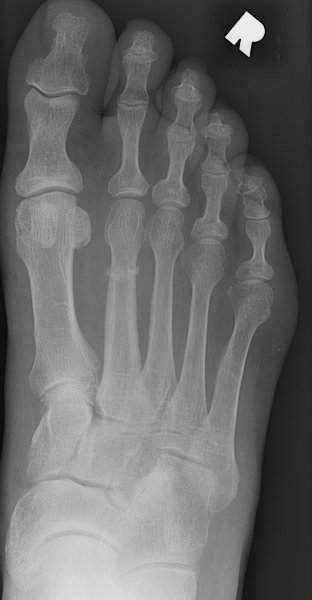

Return to March Fracture